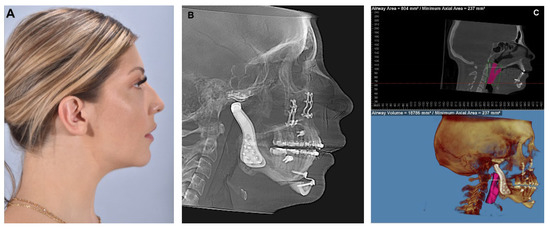

In conclusion, the concomitant approach of TMJR and orthognathic surgery presents a viable treatment option for individuals with complex craniofacial conditions. This combined procedure aims to address both functional and aesthetic concerns (Figure 15), offering a comprehensive solution for patients suffering from TMJ disorders and skeletal malocclusions and does so in one surgical procedure.

Figure 15. (A) The same patient showed previously. Patient was treated in a single surgical stage with bilateral TMJR, Le Fort I osteotomy advancement and genioplasty. The patient is seen 18 months post-surgery showing the maintenance of good facial balance. (B) Lateral cephalogram showing adequate facial profile, correction of the occlusal plane angle, hardware in place with no signs of complications. (C) Airway analysis shows significant improvement in airway space (Airway volume = 18,786 mm3, Minimum Axial Area = 237 mm2).